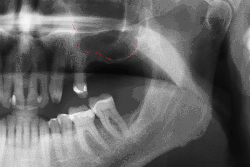

Панорамная рентгенограмма зубных имплантатов, образца 1978 года